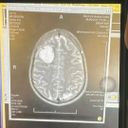

The hospital performed a MRI on my brain, to which we found the unfortunate cause of my seizure.

I have a large tumor on the frontal lobe of my brain, but multiple doctors believe it is benign.